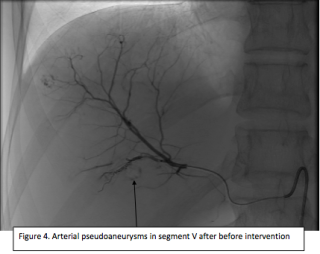

A 60 year old man presented with spoliative anemia. He is not known for cutanous macules around the mouth. An initial work up by colonoscopy and gastroscopy revealed a Helicobacter pylori infection without other significant abnormalities. Subsequently, a magnetic resonance imagery was performed and a 18 mm polyp located in the small intestine was identified (Figure 1). The lesion was not reachable by conventional endoscopy techniques. As endoscopic resection was not feasible, the patient underwent an explorative laparoscopy which enabled the discovery of a lesion in the terminal ileum coupled with an intussuception. The histopathological examinations demonstrated a pedunculated polypoid lesion, measuring 2 x 1.7 cm with a pedicle measuring 2.4 cm consistent with a Peutz-Jegher Syndrome (Figure 2 and Figure 3). Multidisciplinary meeting proposed genetic counselling and endoscopic follow up.